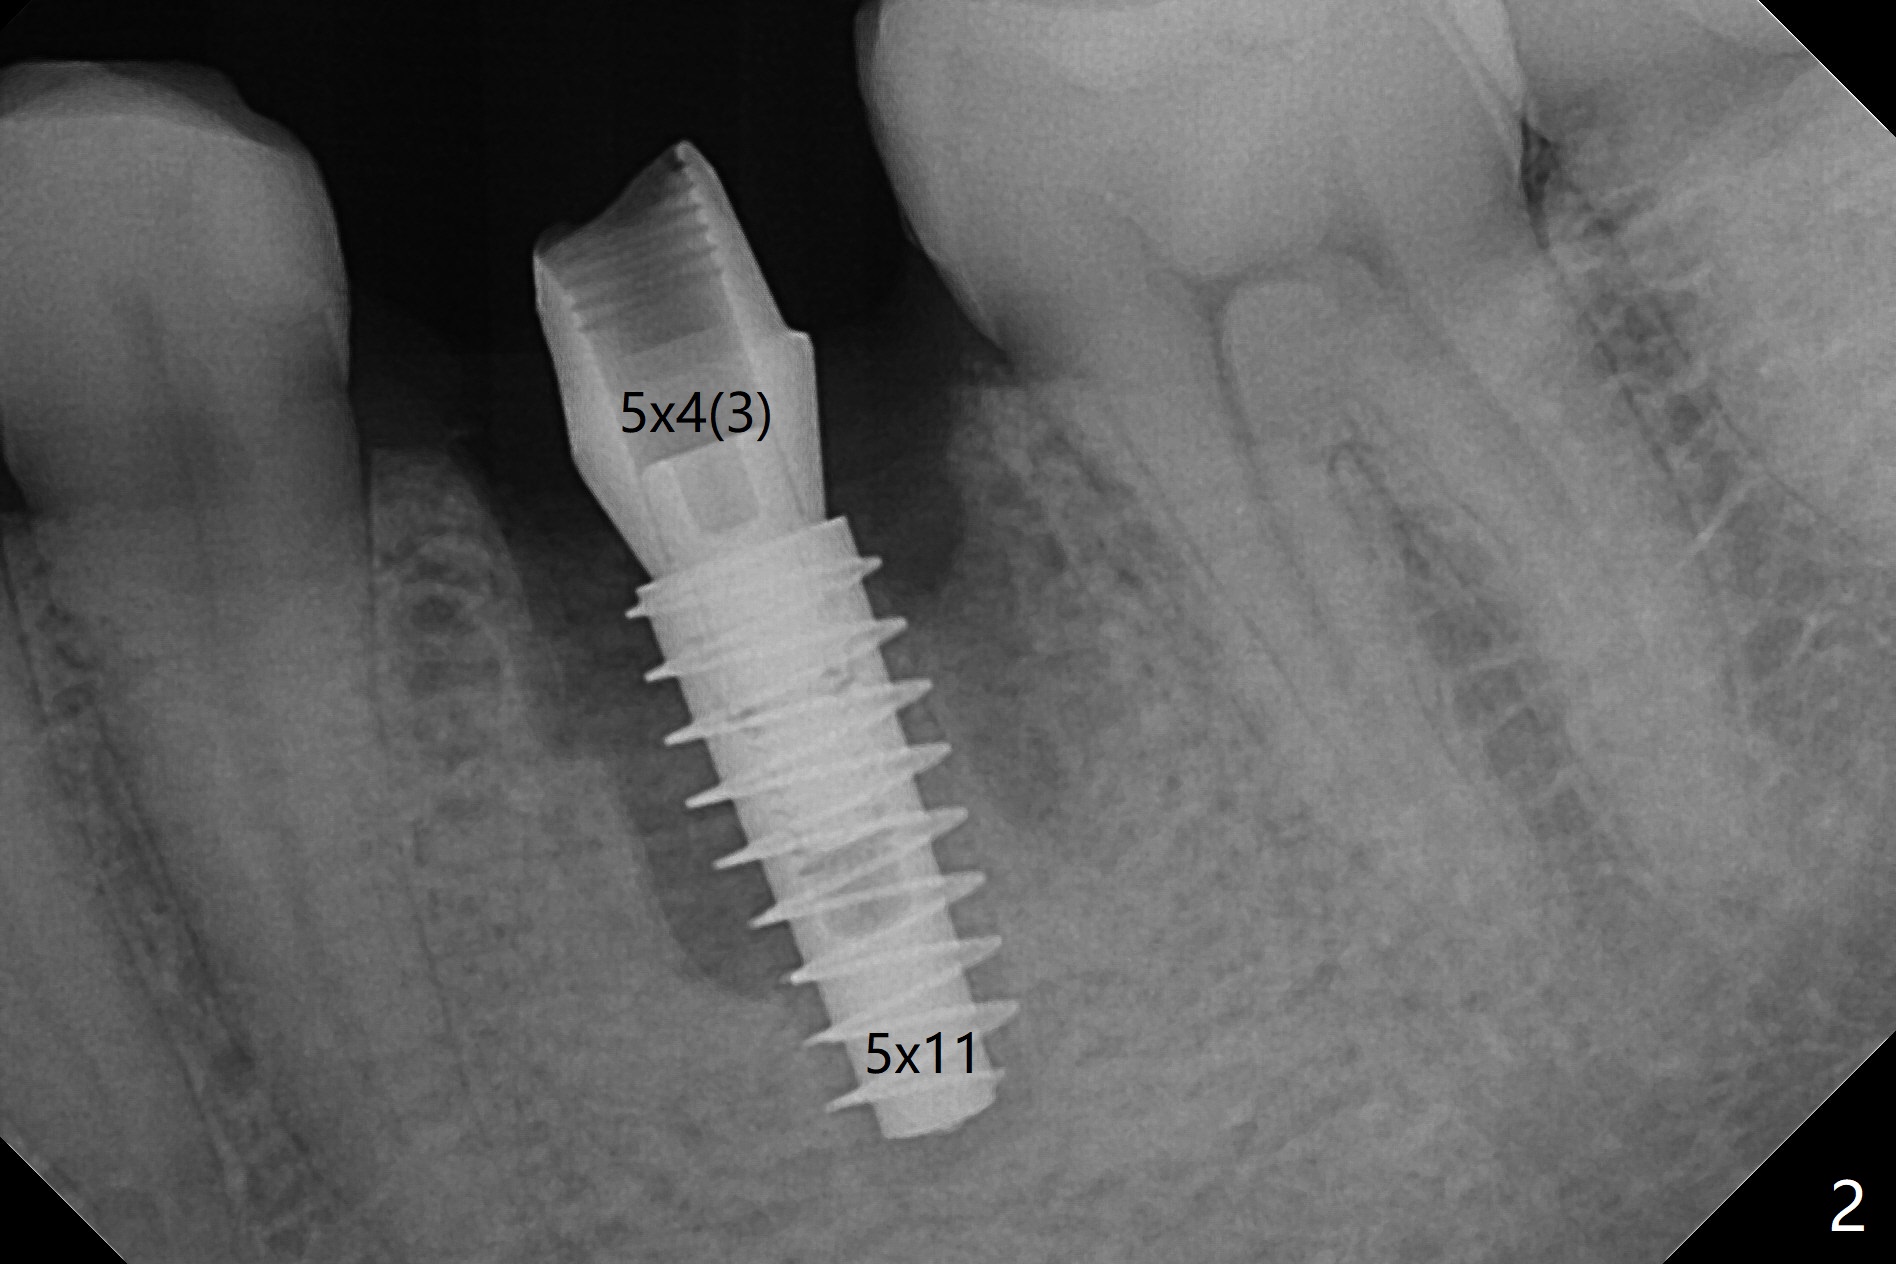

54岁男左下6根管治疗不成功,远中舌侧根弯曲,拔除时牙齿牙根多次断裂,骨质也硬,即使使用2.2毫米钻头也很吃力,钻至11.5毫米深,拍摄根尖片,显示钻洞没有明显偏移(图一),临床观察一致。当钻头直径增大,浅部钻洞,震动大,深部时,震动慢慢减少。为了植入5x11毫米植体,钻头必须4.5毫米,植体还必须反复倒旋转,才能减少扭力至40Ncm。由于没有骨质阻挡,基台放置尚顺利(图二)。拔牙时舌侧远中骨壁破坏,植入粘性骨粉重点放入 (图三:*),表面覆盖一张PRF膜(图四),最后制作临时牙冠。术后1.5月调整临时牙冠,牙槽窝愈合正常(图五)。